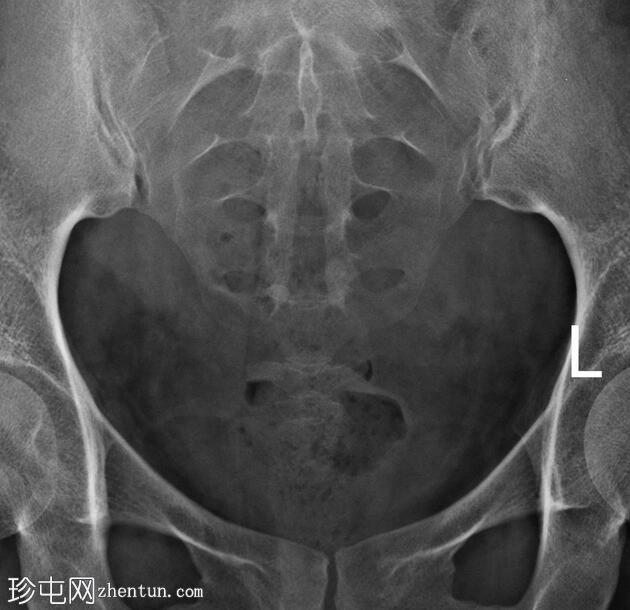

经宫颈管注入造影剂后,子宫腔被充盈。

子宫体位于盆腔中线,呈梭形。